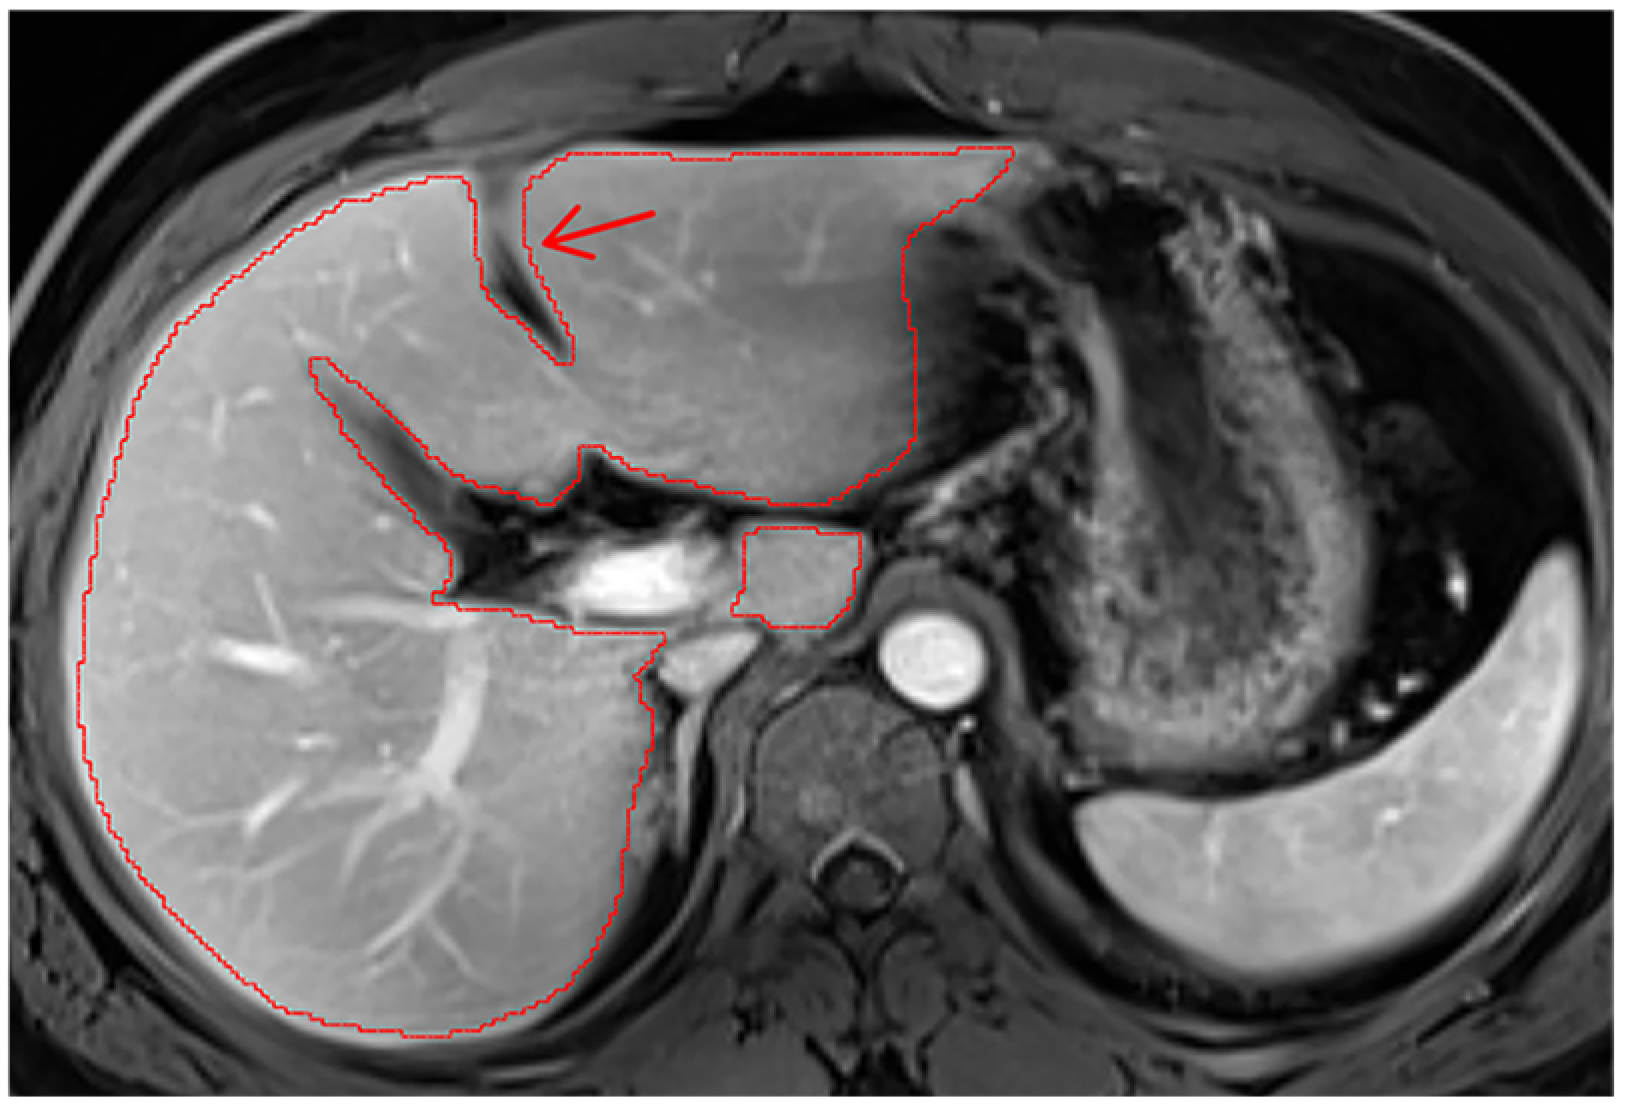

Appendix A.3. Vascular Segmentation